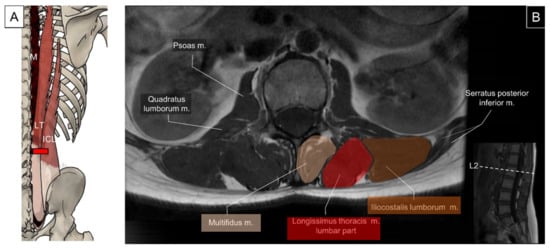

5.2. Iliocostalis Lumborum, Longissimus Thoracis, and Lumbar Multifidus

5.2.1. Anatomy

5.2.2. Sonographic Scanning

5.2.3. Clinical Relevance